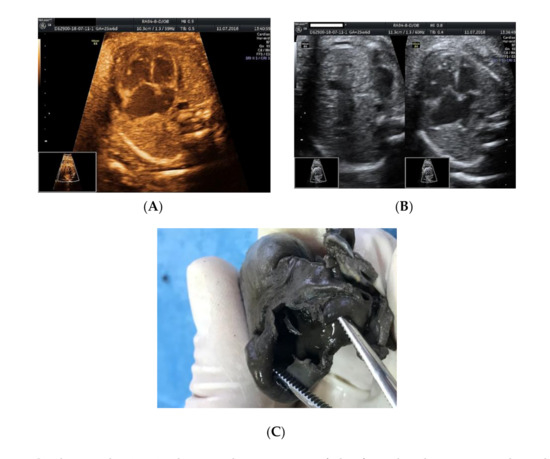

2. Case Presentation